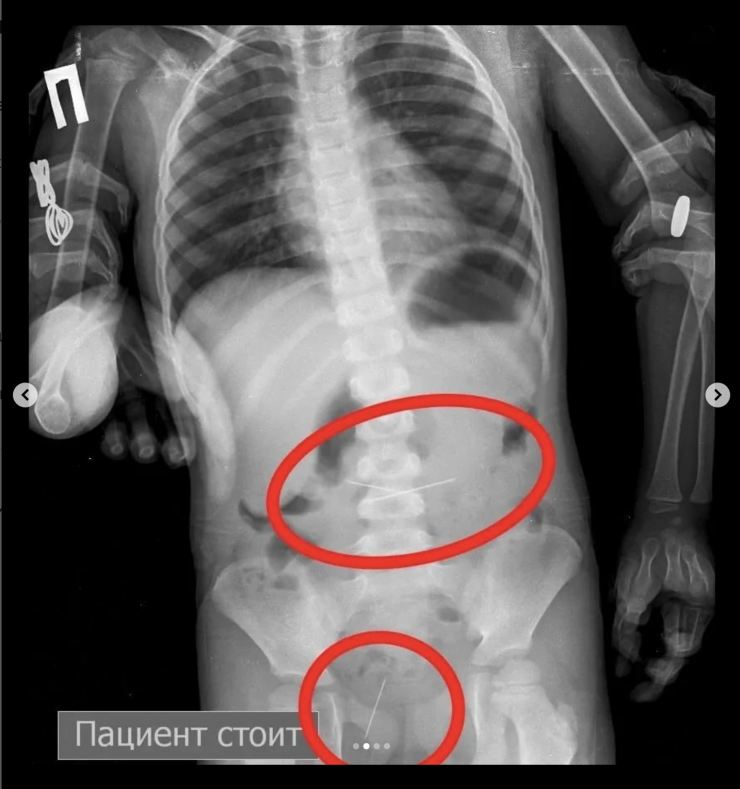

"Позже на контрольной R–грамме брюшной полости обнаружены еще две иглы в верхнем этапе брюшной полости и одна игла в проекции таза. Проведена повторная ЭФГДС, и удалена игла из желудка. Затем при помощи колоноскопии удалена игла, зафиксированная в сигмовидной кишке", - сообщил врач-хирург высшей категории Сейдахмет Чинибеков.

Однако после этого в ходе наблюдения ребенка на контрольной R–грамме брюшной полости обнаружена еще и четвертая игла в проекции таза.

"Проведена колоноскопия, и из сигмовидной кишки удалена последняя игла, которая концом была зафиксирована в слизистую кишечника. В настоящее время ребенок в удовлетворительном состоянии выписан домой", - сообщили врачи.